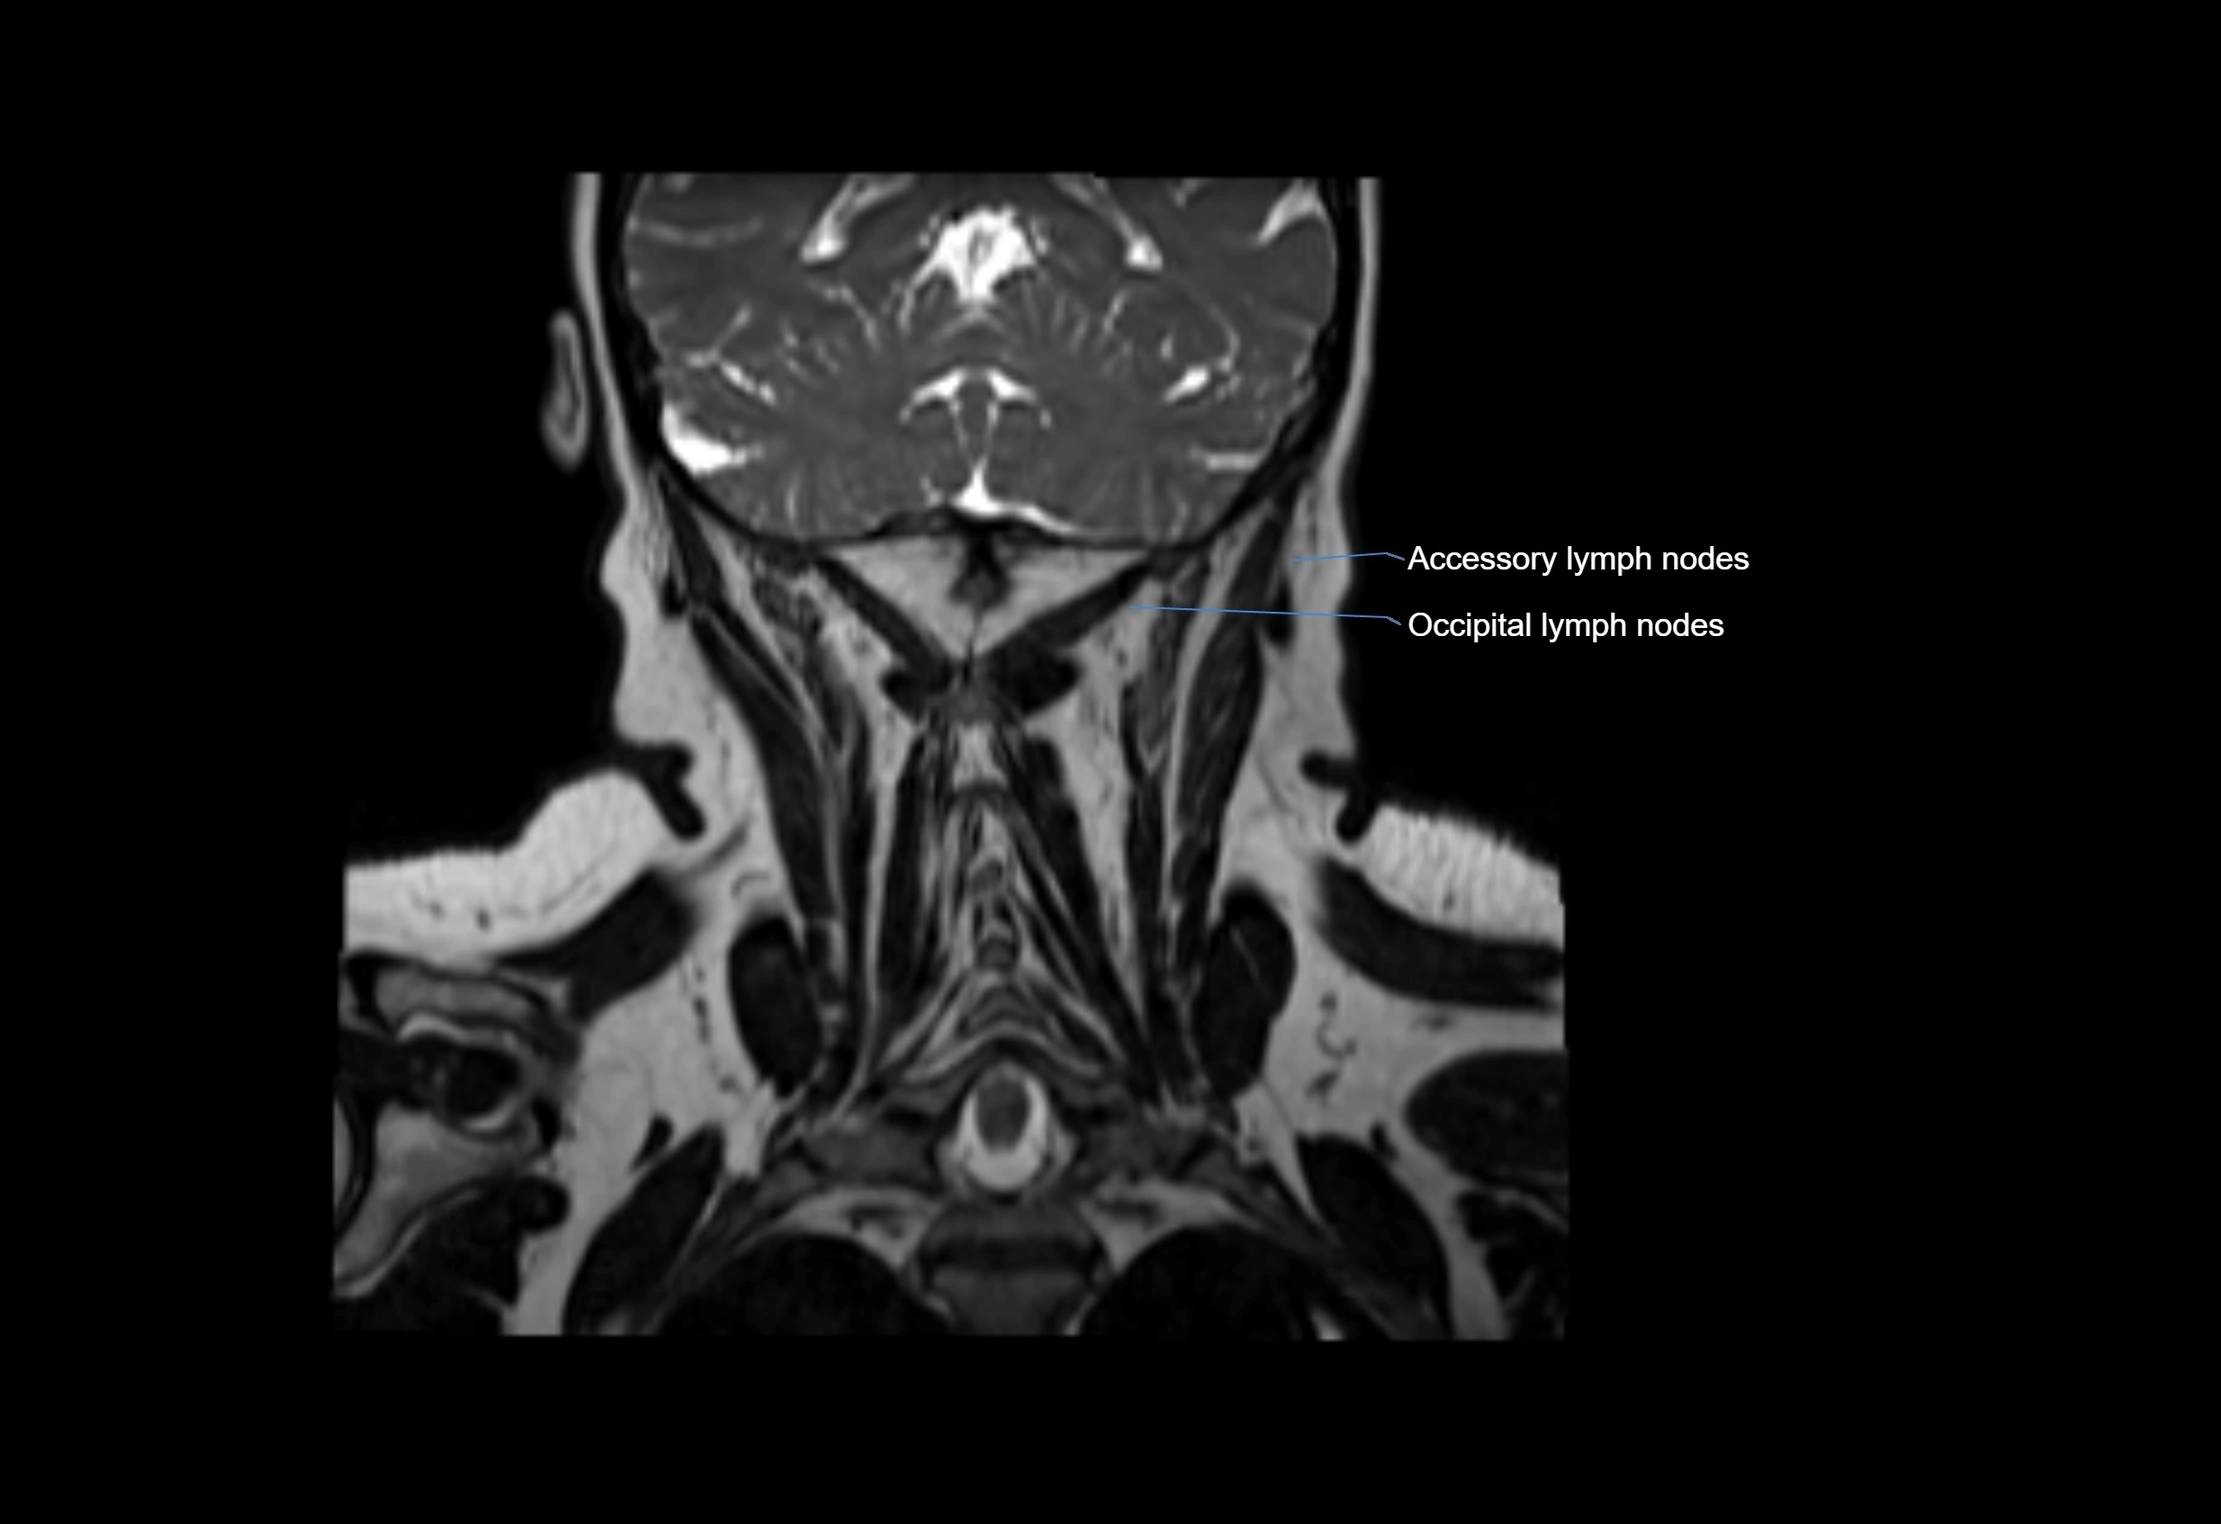

Accessory lymph nodes

Accessory lymph nodes are small, secondary lymph nodes located along the main facial and cervical lymphatic chains, often adjacent to primary lymph nodes, such as preauricular, submandibular, or occipital nodes. They are typically less than 5 mm in diameter, embedded within subcutaneous fat or connective tissue, and may be variable in number and location. These nodes provide additional filtration and immune surveillance for lymph collected from the face, scalp, and neck regions. Accessory lymph nodes are usually non-palpable in healthy individuals but may enlarge in response to infection, inflammation, or metastasis, making them clinically significant.

Location

• Found along primary lymph node chains, including preauricular, submandibular, parotid, and occipital regions

• Embedded in subcutaneous fat or superficial fascia, often lateral or posterior to primary nodes

• Variable in number; may occur unilaterally or bilaterally, depending on individual anatomy

MRI Appearance

T2-weighted images:

• Nodes show intermediate signal, with surrounding fat bright

• Useful for detecting edema, inflammation, or infiltration

• Fatty hilum may appear slightly hyperintense relative to cortex